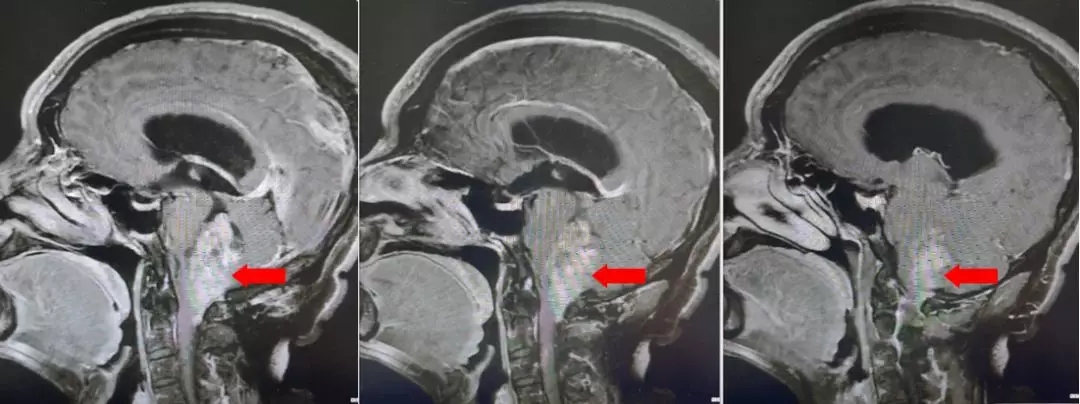

颅脑核磁平扫加增强扫描:

第四脑室内见一巨大形态不规则的异常信号影,肿瘤信号不均匀,T1W1呈略低信号影,T2W1呈稍高及高信号影,增强扫描可见肿瘤不均匀明显强化。肿瘤充满整个四脑室,大小约44*37*55mm,上方接近四脑室顶部,下方至颈2脊髓平面上方,已经部分侵袭桥脑、延髓,局部边界不清,无明显间隙,脑干局部明显受压变形。肿瘤上方脑室系统扩张,出现梗阻性脑积水征象。

影像诊断:1.第四脑室内占位性病变,室管膜瘤可能性大;2.梗阻性脑积水。